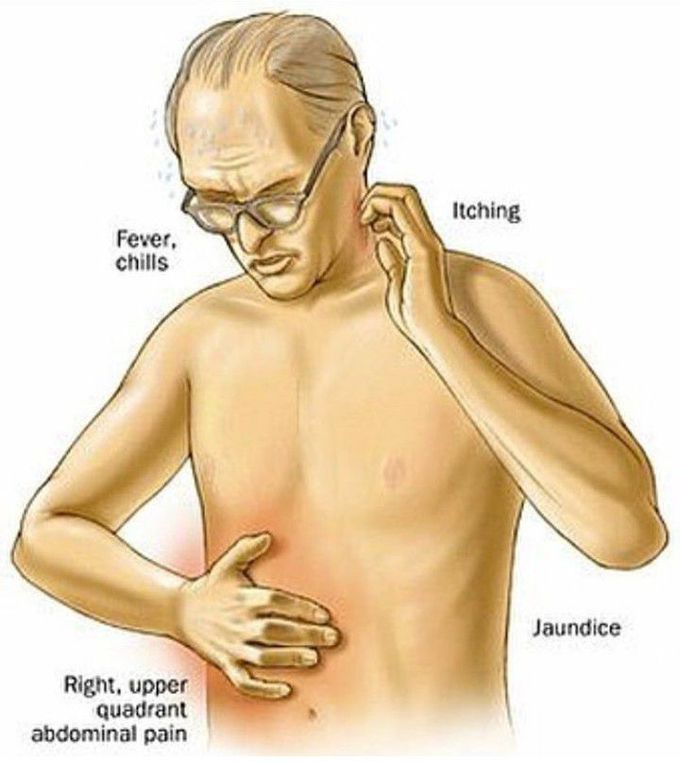

Фотографии и изображения, связанные с симптомами первичного склерозирующего холангита